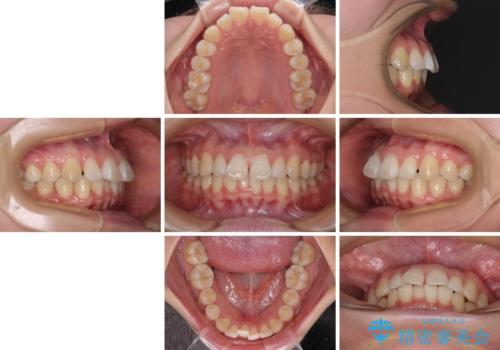

- 上顎前歯の隙間を気にして来院された患者様です。

下顎前歯が上顎前歯に食い込むような咬み合わせにより、上顎前歯が開いてしまっていたため、咬合高径の挙上により突き上げを改善するよう、インビザラインにより矯正治療を行うこととしました。

咬合高径の挙上により上顎前歯の突出感も改善することができ、整った口元となりました。